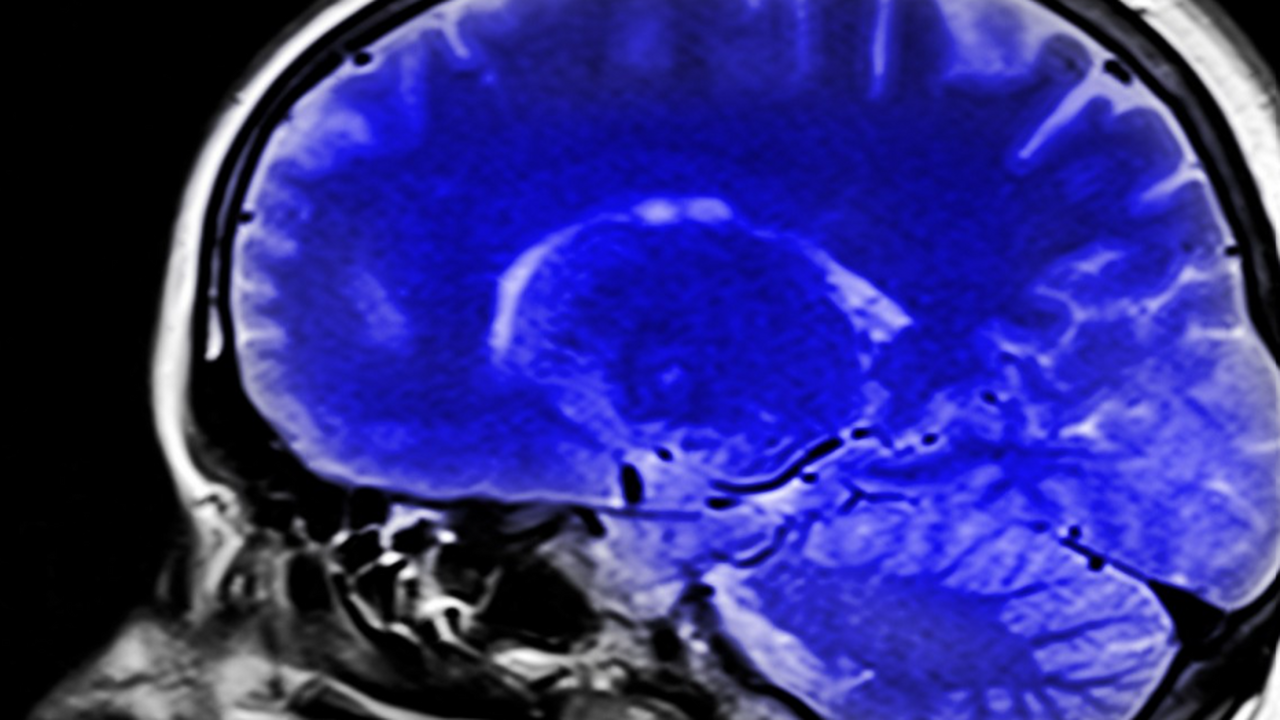

Ученые из Сколтеха, Института искусственного интеллекта AIRI и МГУ разработали уникальную интерактивную платформу, которая ускорит создание «умных» систем для лечения болезни Паркинсона. Этот инструмент позволяет тестировать и обучать алгоритмы глубокой стимуляции мозга в виртуальной, но крайне реалистичной среде.

Глубокая стимуляция мозга (DBS) — это эффективный метод борьбы с симптомами Паркинсона, когда в мозг имплантируют электроды. Однако у технологии есть серьезный недостаток: из-за изменений в тканях мозга прибор требует постоянной ручной настройки врачом, что неудобно и для пациента, и для доктора.

Платформа создает цифровую модель мозга, которая точно имитирует реакцию нейронов на стимуляцию. Она показывает, как различные зоны мозга активируются и взаимодействуют друг с другом в режиме реального времени. Система обладает высокой вычислительной мощностью, что позволяет моделировать разные состояния пациента — от сна до сложных процессов вроде ходьбы.